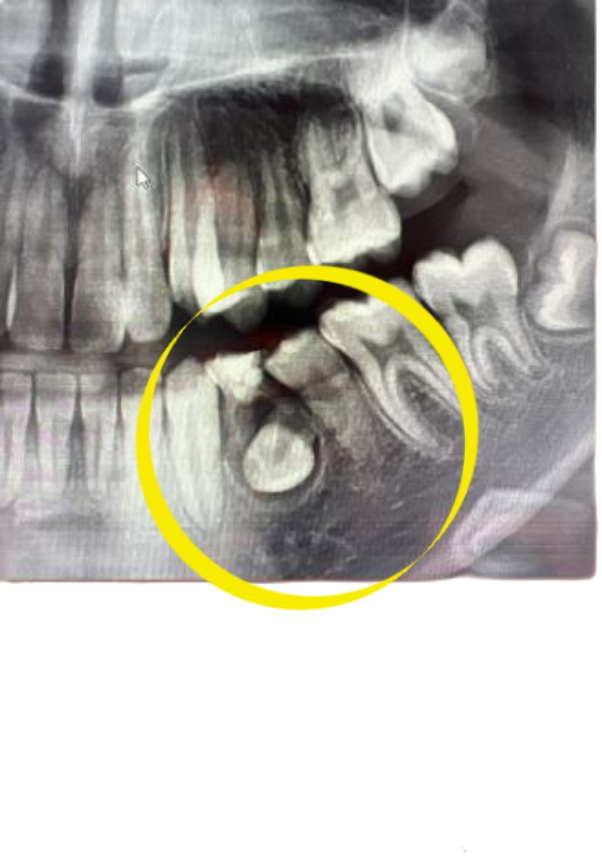

하지만 사진으로 봤을 경우에는 유치의 뿌리 쪽에 염증이 생겨서 고름이 차이는 것으로 보입니다.

이런 경우에는 유치를 발치를해주는 것이 좋으며 발치를 했을 때는 매복되어 있는 치아를 맹출 시키거나 보철 치료 등으로 치아가 없는 부위를 수복해 주는 것이 좋습니다.

다만, 사진상으로 확실하진 않으나 영구치 치관(치아머리) 주위가 낭포가 형성된 것이 맞다고 병리학적으로 판단되면 영구치도 사용하기 어려울 수도 있습니다.